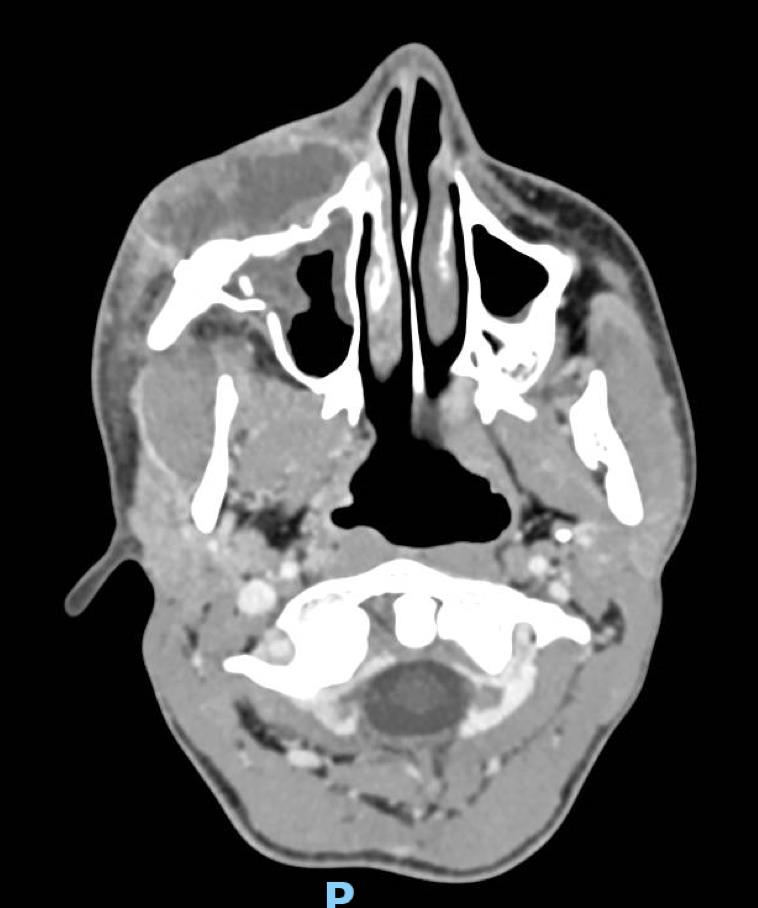

De garde, vous êtes appelé en salle de surveillance post-interventionnelle (SSPI) dans votre hôpital où vient d'être admis un patient conduit sur place par le service d'aide médicale d'urgence (Samu). Il s’agit d’un jeune homme de 20 ans, Monsieur D. Il aurait été victime, entre autres, d’un tir de Flash-Ball lors d’une rixe. Le projectile l’a atteint au niveau de la pommette et de l’orbite droites. Il présente une plaie de la région jugale haute, un œdème des paupières supérieure et inférieure. Vous ne visualisez pas le globe oculaire spontanément. Il est hémodynamiquement stable.

Traumatisme orbitaire = à risque de fracture des parois de l’orbite et donc d’incarcération d’un muscle oculomoteur.